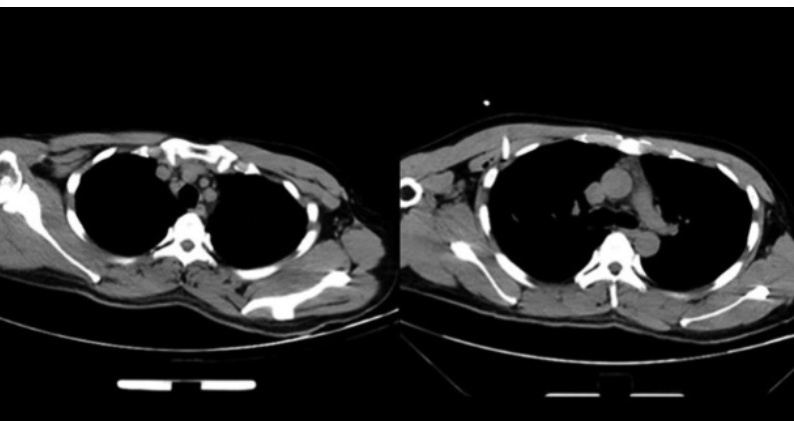

病史摘要:患者主因“检查发现肺结节8年余”入院。八年前胸部CT提示左肺下叶少许增殖灶,此后规律在多家医院复查。近期在当地医院检查发现左肺下叶背段结节伴空洞,遂来院进一步诊治。患者近期有咳嗽咳痰,无其他不适,发病以来精神、胃纳、睡眠、二便及体重无明显改变。 诊疗过程:体格检查未提及。多次胸部CT检查,从2017年至2025年,病灶从磨玻璃结节逐渐发展为实性结节伴空洞,呈现典型浸润性癌影像表现